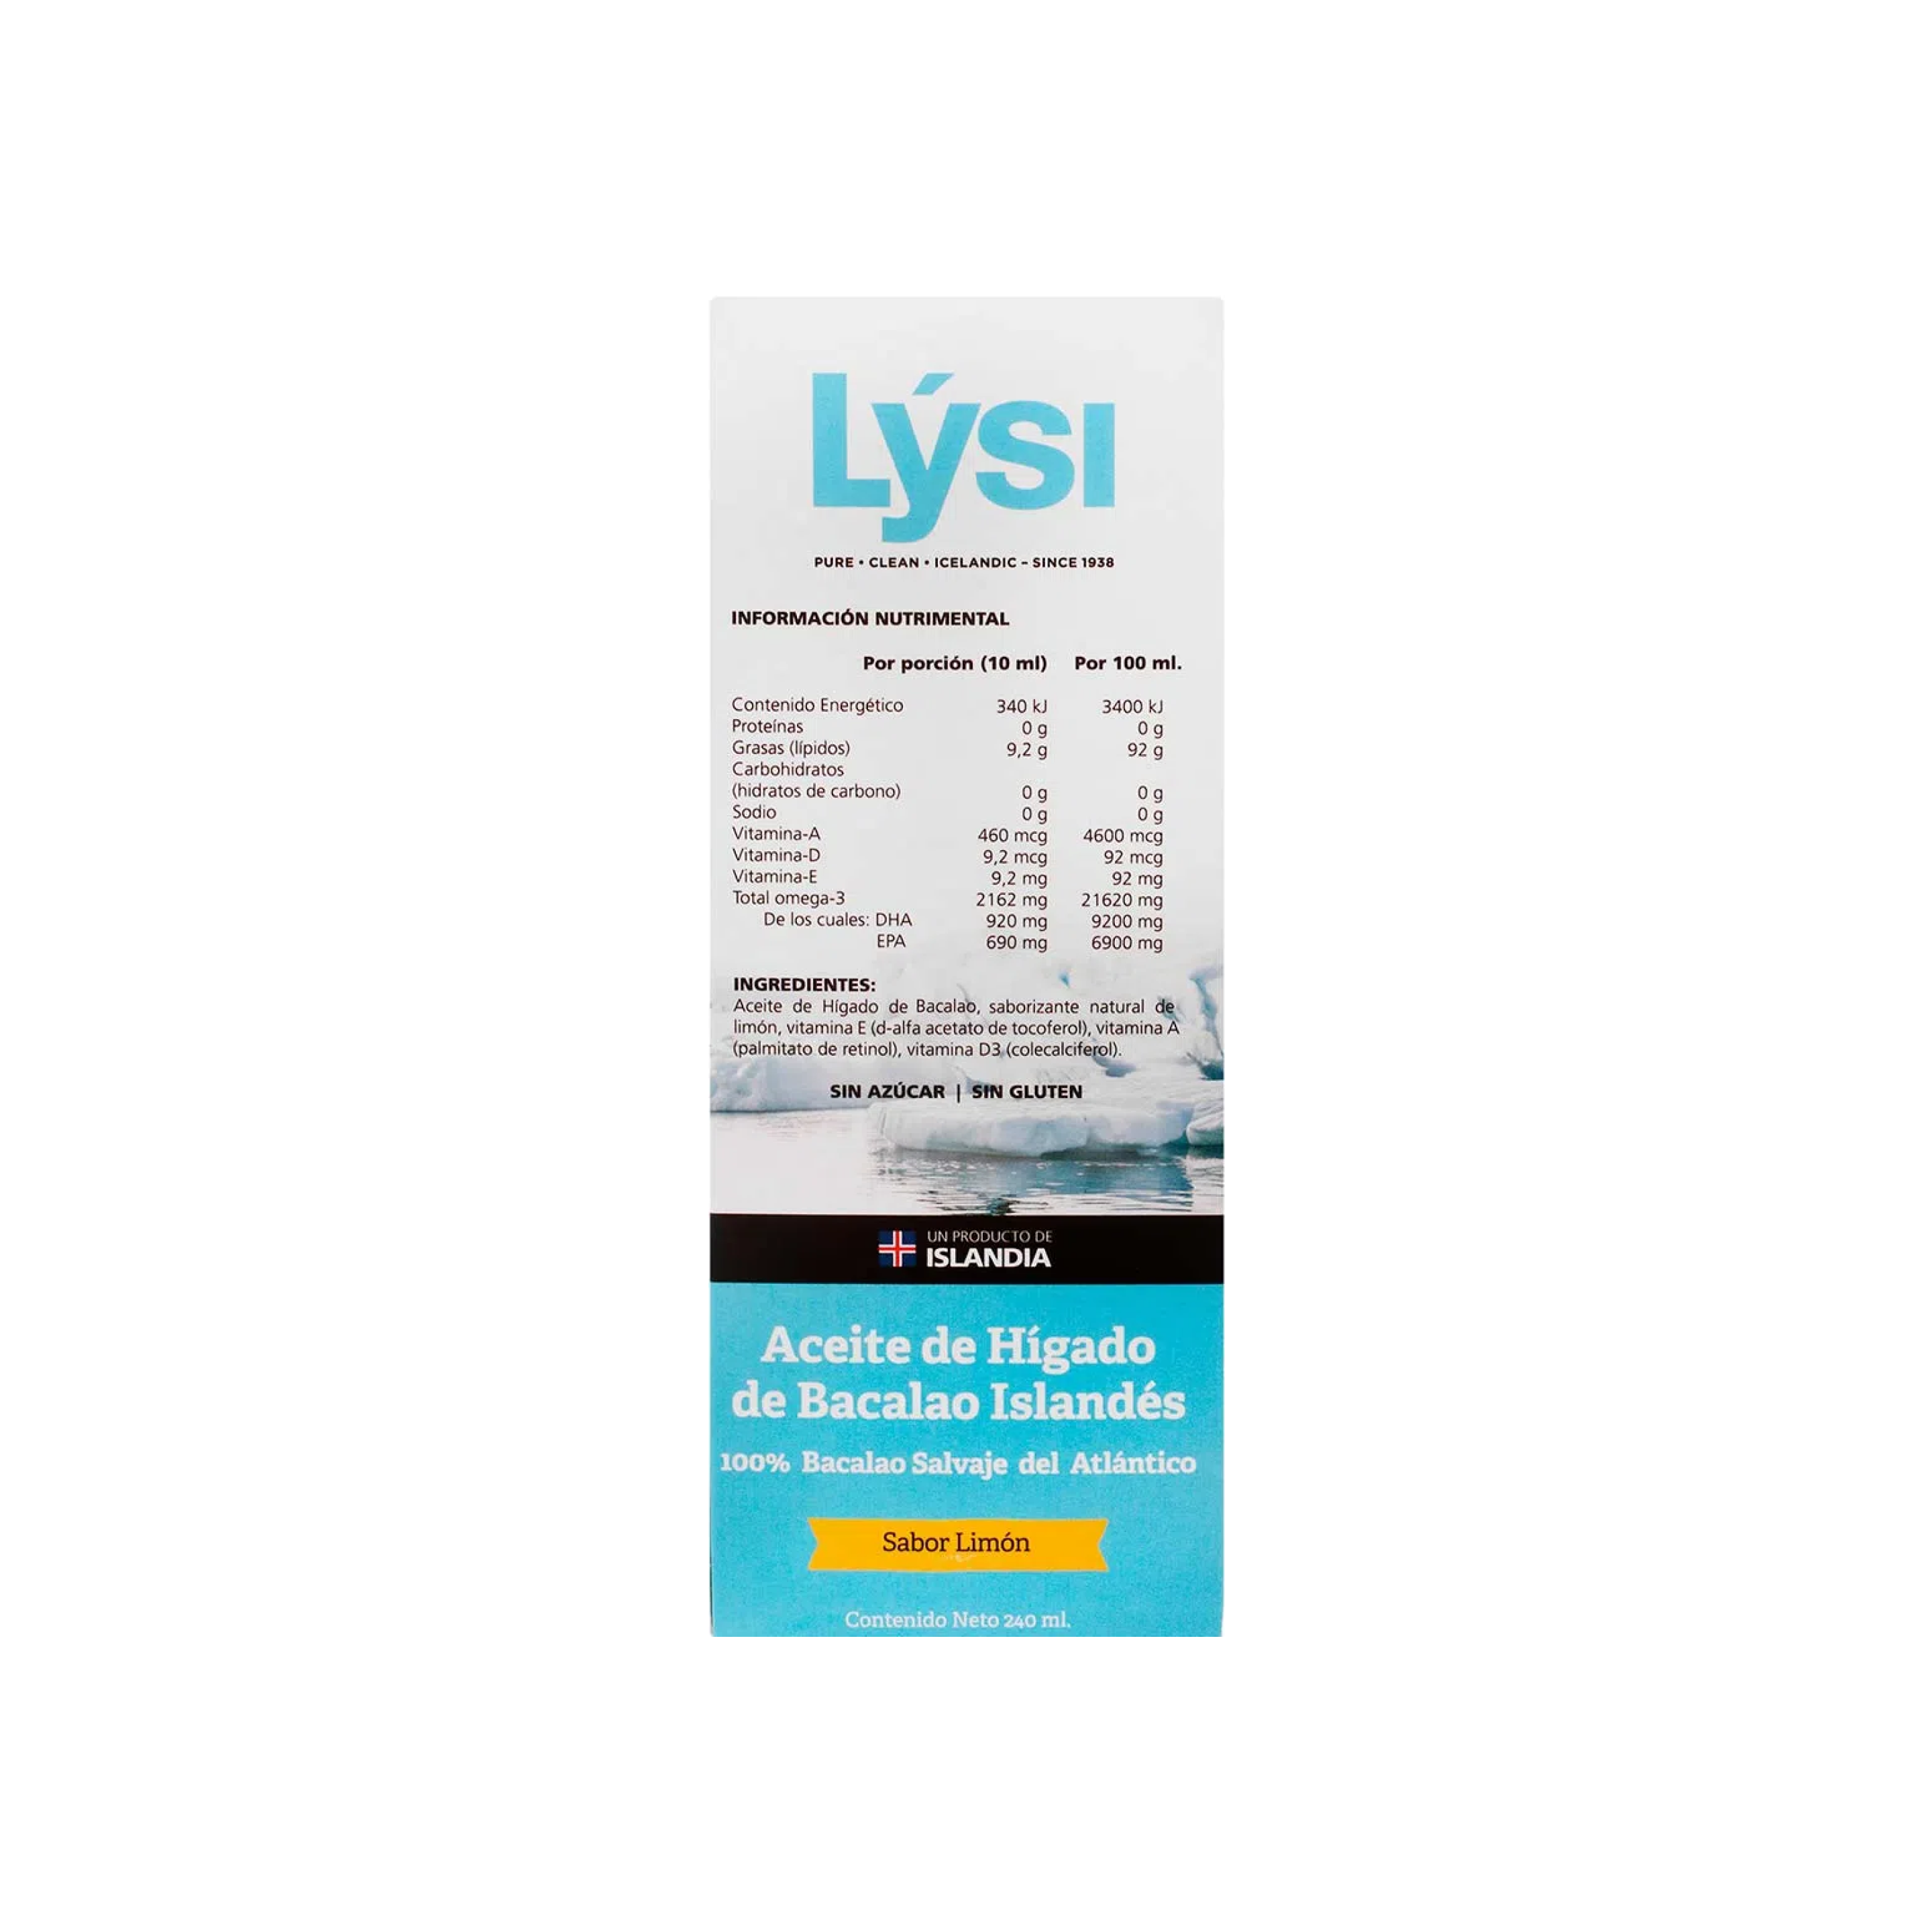

Descubre Los Sorprendentes Beneficios Del Omega 3 Y Cómo Ayuda Al

beneficioso.es

beneficioso.es